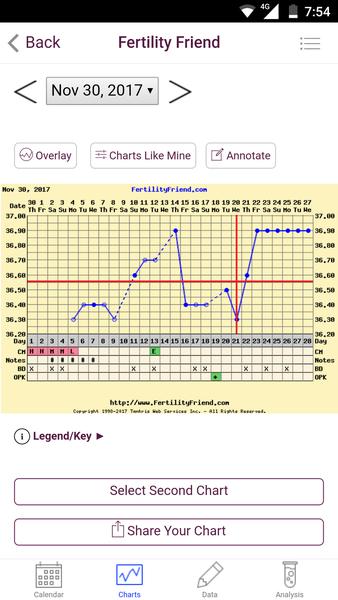

@wewe28 ahojky, to iste ako minuly týždeň, slabý ružový duch na 25kovom teste, na 10kovom ani náznak, cecky už o číslo väčšie ako zvyčajne, ráno nevoľnosť ako hovado, biely hustý výtok bez zápachu, fakt tomu nechápem... no a keď berieme od spinenia je to 13 dni, keď to berieme že to bola MS (čo podľa mna nebola) tak 13 DC, zajtra začínam poslednú krabičku Duphastonu a potom kontrola u gynekológa..prikladám fotky ale nemyslím si že to na mobile vidno, je to viac vidno voľným okom aj po rozobratí ale cez mobil nie. Španielska dedina toto, ale asi sa na to vykaslem len ide Silvester a neviem či si teraz dať pozor s alkoholom alebo nie

@chuchu86 a prečo mi graf oznacil ovu 21ho?presne toto som nevedela,lebo tento označuje tak a iný presne ako píšeš až 22ho..necítim sa práveže nijako 😂 brucho ma bolelo 2dni teraz ale to budú skôr čreva a kapustnica 😂😂 testovať veľmi nechcem,nedávam tomu veľmi nádej..ale si zlatá že aspoň ty jediná si reagovala..😁 už sa mi viackrát stalo,že mi tu nikto nereaguje na príspevok..čo už 😂 no teda držím ti palce aby ms už neprišla..neskúšala si ešte test?

@wewe28 však práve, že to by som bola riadne na hlavu pokladať to spinenie za MS nakoľko to nič nebolo...ešte ma napadlo ako som tu čítala že niektorým neukázal tehu test do 8-9 týždňov 2 čiarky čo by vysvetľovalo moju situáciu ale to by bolo už plne fantázie takze to neberiem ani do úvahy, možno sa mi búria hormóny, kto vie prečo tie nevoľnosti a plne cecky apod 😂 gynekológ neordinuje medzi sviatkami, takze krv vylúčená...ale muž ma “prekvapil” dvoma testami (chudák nevedel čo kupuje, sú to 25ky) ktoré si MUSÍM zobrať na chatu a testnut na Silvestra, ale povedala som mu, že nech s tým konečne prestane a nič na tom teste nie je a koniec, ideme ďalej...a na Silvestra budem toľko piť, koľko mi povie telo - lebo ak som aj tehotná (fantazírujme) tak si telo aj tak povie nevoľnosťami...iné ma nenapadá, svet sa nezrúti 🙂